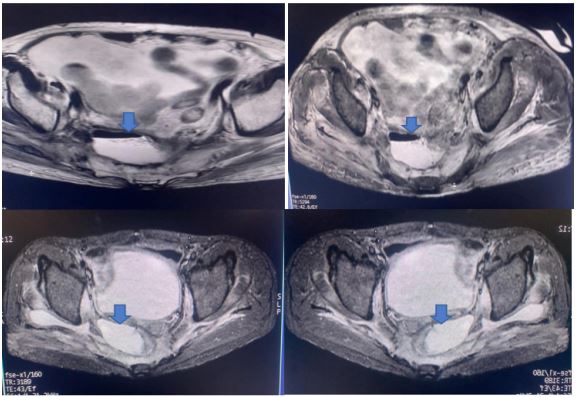

Figure 3: MRI pelvis showing collection in presacral area.

Case capsule 1

A 59-year-old man has complained of pus and mucus discharge from the anal region, as well as intermittent fever episodes, for the past two years. Three years ago, he developed symptoms of per rectal bleeding and was diagnosed with Carcinoma rectum, for which he received three cycles of neoadjuvant radiotherapy followed by laparoscopic anterior resection with a defuncting descending colostomy. He was discharged on post-operative day 8, with no issues reported. Adjuvant Chemotherapy was administered in 13 cycles. After 6 months of surgery, a CT abdomen was performed, which showed post-op changes in the pelvis with Pelvic peritoneal fat stranding and widening of the presacral space. He was having repeated episodes of fever with chills and pus discharge per anus that were resolved with IV antibiotics. After 6 months, an MRI of the pelvis revealed a significant collection of size 9.1 x 5.2 x 8.8 cm with air loculi at the presacral area-most likely a controlled leak (Figure 2). The conservative approach was continued for another six weeks, during which an intermittent fever with mucus and pus discharge from the anal region persisted. A colonoscopy was performed, which showed the cavity and confirmed the findings (Figure 4). Endovac sponges were sutured to RT and placed directly into the cavity with the help of a colonoscope after debriding and irrigating the cavity. After applying post-E-VAC therapy, the patient improved and had no fever after 48 hours. The procedure was repeated on an OPD basis four more times, with the endovac in place for five days each. At each session of endoscopy, there was a reduction in the size of the sponge used and considerable improvement in terms of the size of the cavity and the amount of slough (Figure 5). The cavity completely healed 10 weeks after E-VAC therapy, and the patient has been asymptomatic for the past 4 months. A CT scan showed complete resolution of the leak.